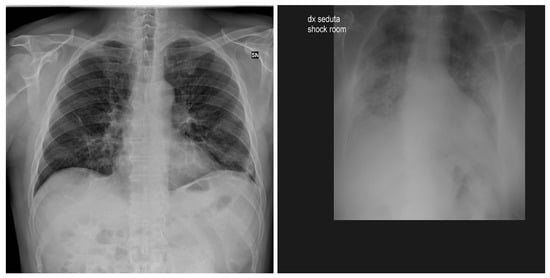

3.3. BIMCV COVID19+

3.4. RSNA